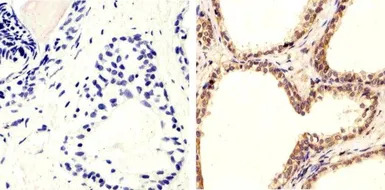

IHC-P analysis of mouse prostate tissue using GTX60929 PTEN (phospho Ser370) antibody.

Right : Primary antibody

Left : Negative control without primary antibody

Antigen retrieval : 10mM sodium citrate (pH 6.0), microwaved for 8-15 min

Dilution : 1:20